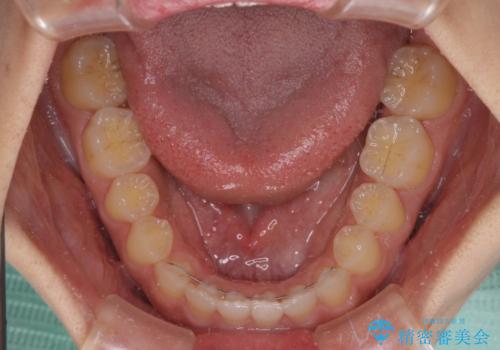

- 後戻りによる上下前歯の隙間を気にして来院された患者様です。

歯列不正はそれほど大きくなかったため、インビザライン・ライトを用いて矯正治療を行うこととしました。

無理のないペースで治療を進め、9ヶ月で終えることができました。